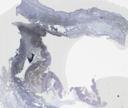

41-11b: Lymphozytäre Colitis (CD3)